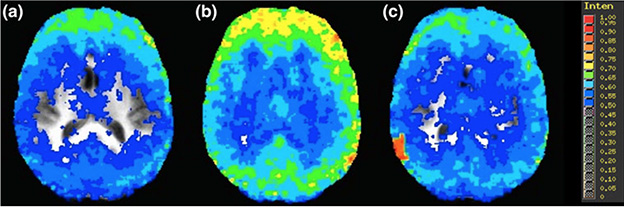

These images show a person’s brain before drinking 6 ounces of whisky (left), immediately after drinking the whisky (middle) and 90 mins after drinking (right). In these brain scans, blue represents a more chaotic brain, while yellow shows less chaos.